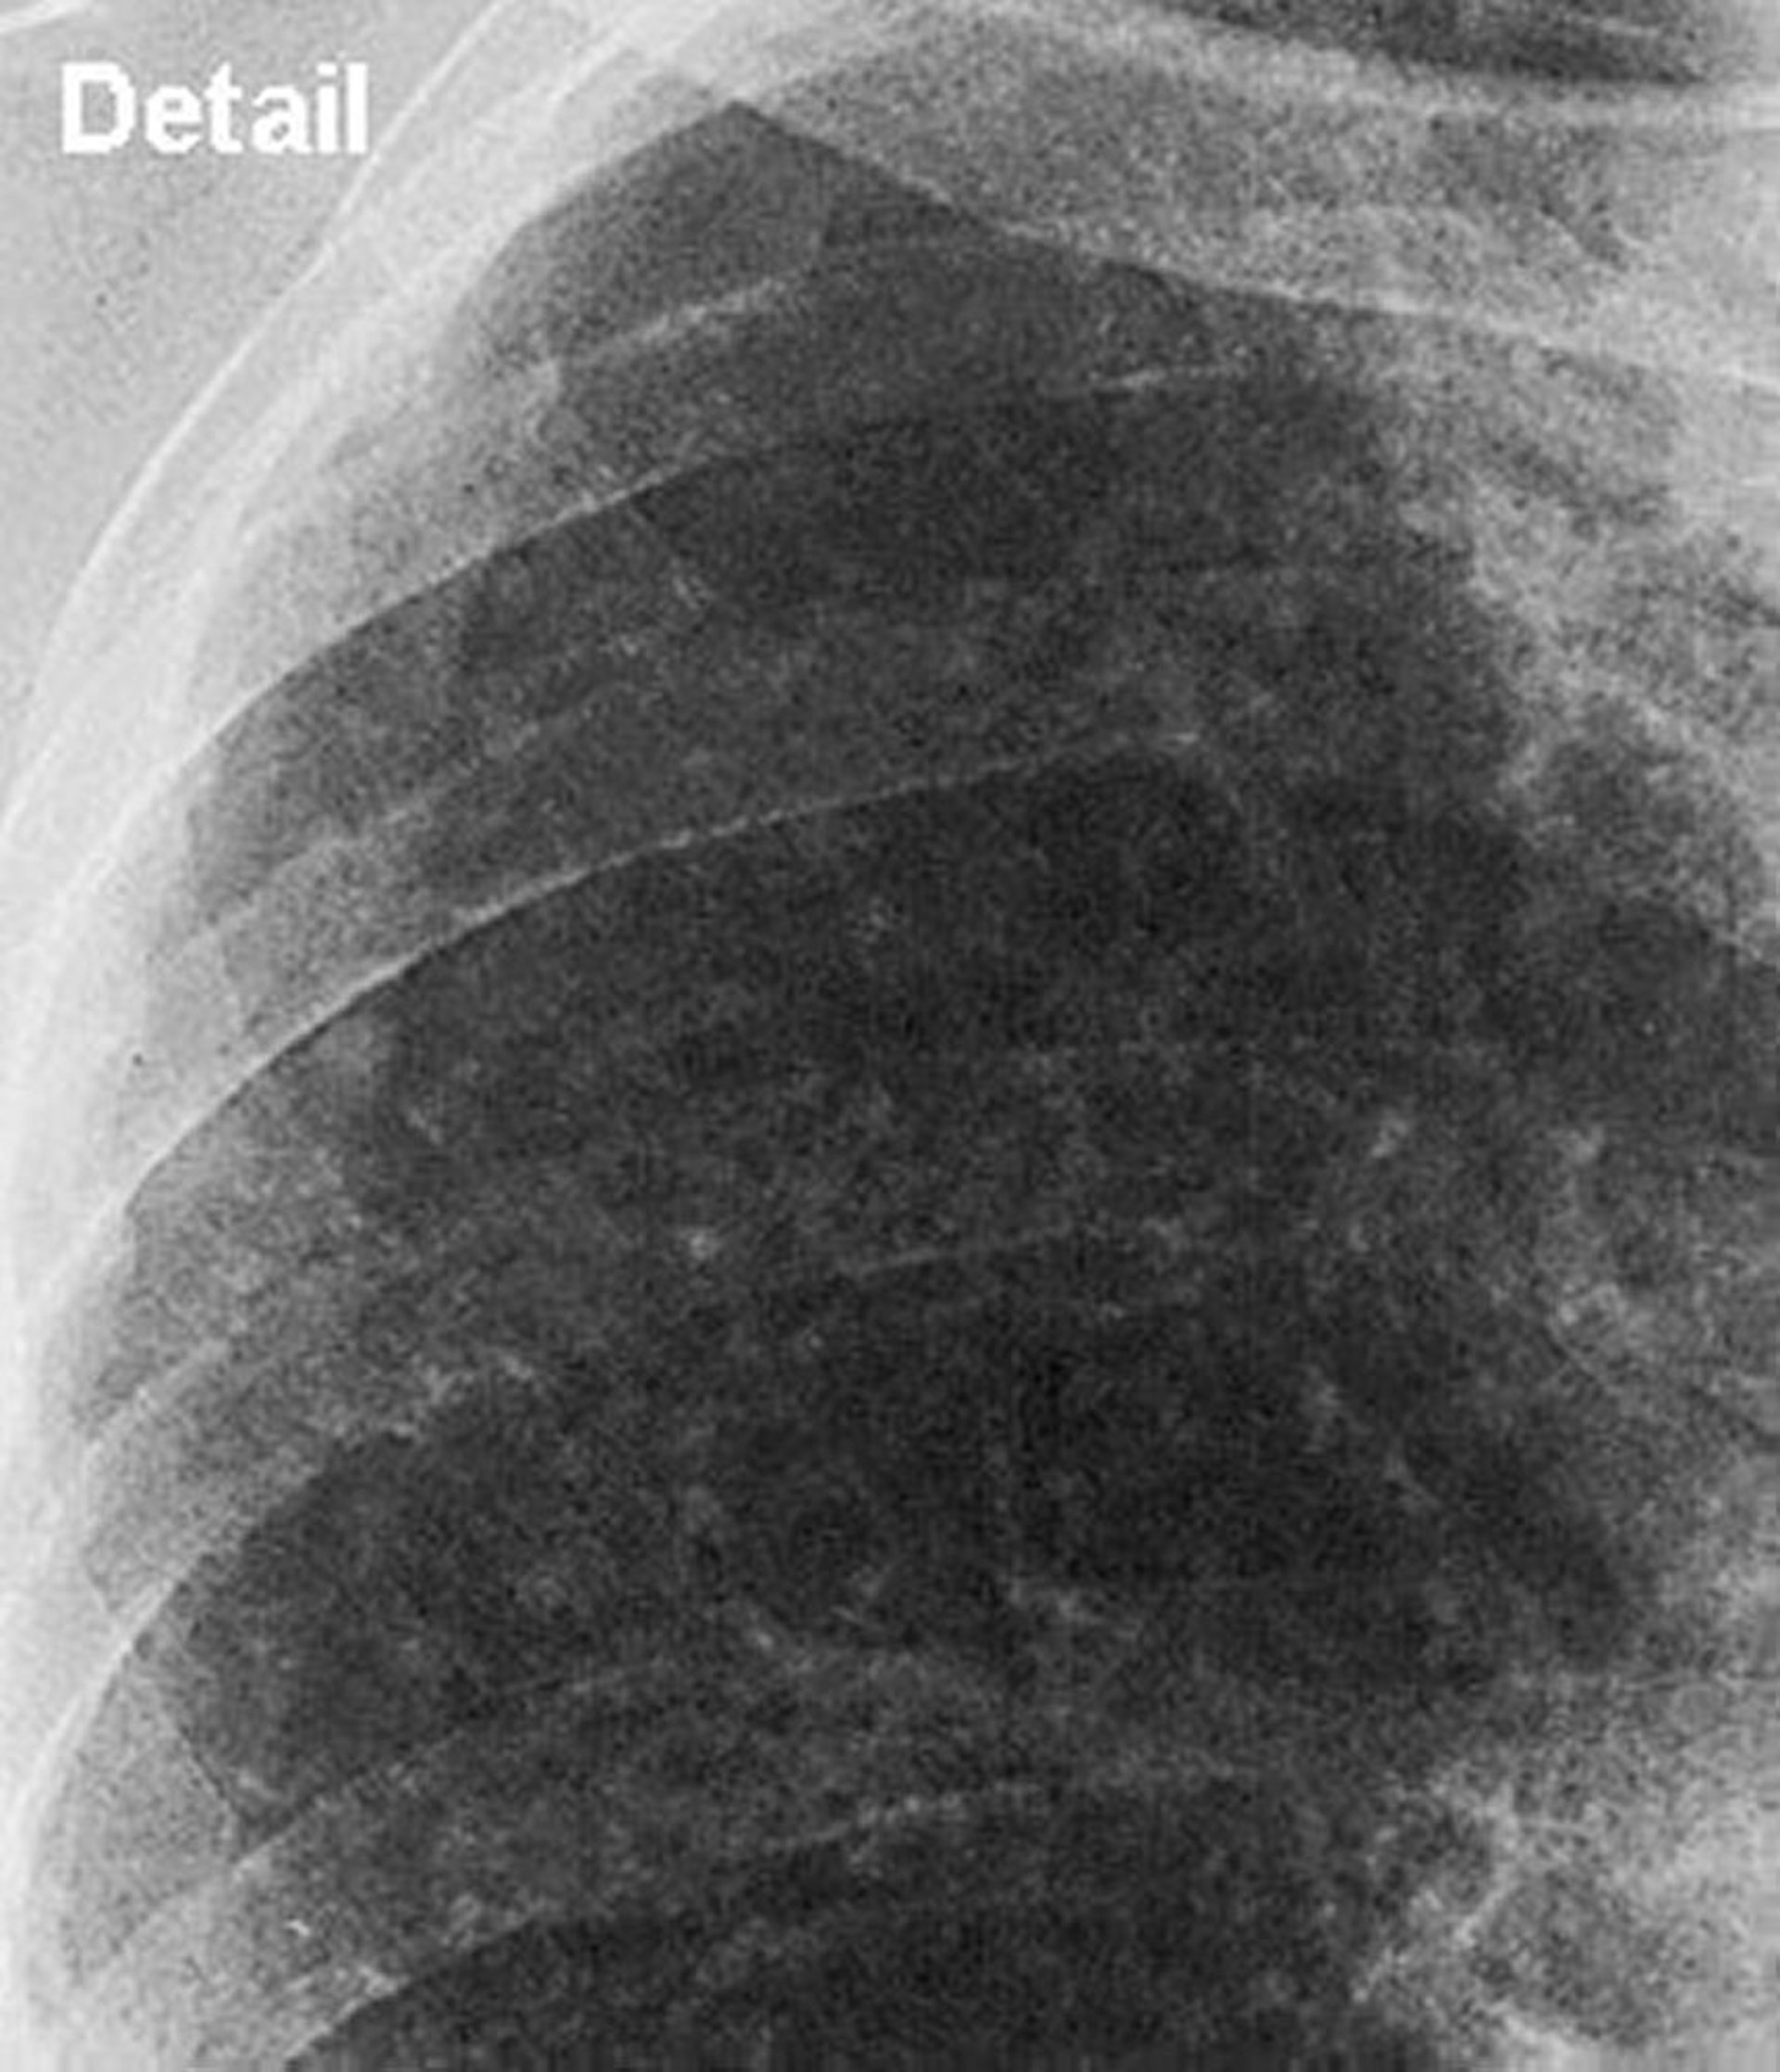

Silikose - einfach (oberes Lungenfeld)

Nahaufnahme des oberen Lungenfeldes bei einfacher Silikose.